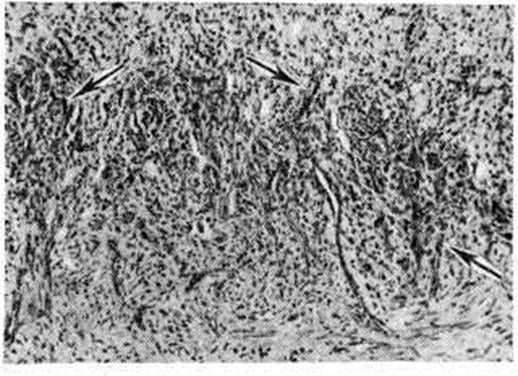

Рис. 1.

Очаговые кровоизлияния, узелки и бляшки на коже в области голеностопного сустава у больного саркомой Капоши.

Макроскопически поражения кожи представлены различными элементами и их сочетанием — пятнами, бляшками, узлами с очагами кровоизлияния (рисунок 1). Пятна красновато-синюшного или красновато-бурого цвета, обычно множественные, до 5 сантиметров в диаметре, различных очертаний. Они резко отграничены от окружающей кожи, поверхность их, как правило, гладкая, иногда отмечается небольшое шелушение. С течением времени цвет пятен приобретает все более синюшный и тёмный оттенок. У части больных ранним проявлением Капоши саркома множественная геморрагическая являются полусферические или плоские узелки размером до горошины, розоватого, а затем красновато-синюшного или бурого цвета, безболезненные. Постепенно увеличиваясь в размерах и количестве, узелки группируются в виде дуг и колец, центр отдельных узелков западает, они становятся более плотными. В процессе дальнейшего прогрессирования на месте пятен и узелков развиваются бляшки и опухолевые узлы. Бляшки диаметром около 5 см имеют округлые или овальные очертания, поверхность их чаще неровная (типа апельсиновой корки), видны телеангиэктазии (смотри полный свод знаний). Цвет бляшек от буровато-красного до коричневато-синюшного, реже он приближается к цвету нормальной кожи. Опухолевые узлы диаметром от 1 до 5 сантиметров имеют полушаровидную форму, плотно-эластическую консистенцию, значительно возвышаются над уровнем кожи. Покрывающая их кожа гладкая, блестящая, красновато-синюшного цвета. Опухоли могут оставаться изолированными или сливаться между собой, способны изъязвляться.

Излюбленной локализацией Капоши саркома множественная геморрагическая являются конечности, особенно передние поверхности голеней. Редкие первичные локализации Капоши саркома множественная геморрагическая — ушные раковины, область живота, половой член, веки и конъюнктива глаз. Характерны многоочаговость и симметричность поражения. По мере прогрессирования процесса у части больных происходит изъязвление опухолевидно-инфильтративных очагов с образованием глубоких язв неправильных очертаний; при локализации на конечностях развивается слоновость. Опухолевидные образования чаще безболезненны, изредка чувствительны или сопровождаются зудом, в отдельных случаях мучительно болезненны. Иногда наблюдается генерализация процесса с появлением кровоточащих опухолевых узлов во внутренних органах (в желудочно-кишечного тракте, печени, лёгких, лимфатических, узлах, костях). Вопрос о возможности самопроизвольной инволюции части высыпаний при Капоши саркома множественная геморрагическая, в частности узелковых и опухолевидных, остаётся спорным.